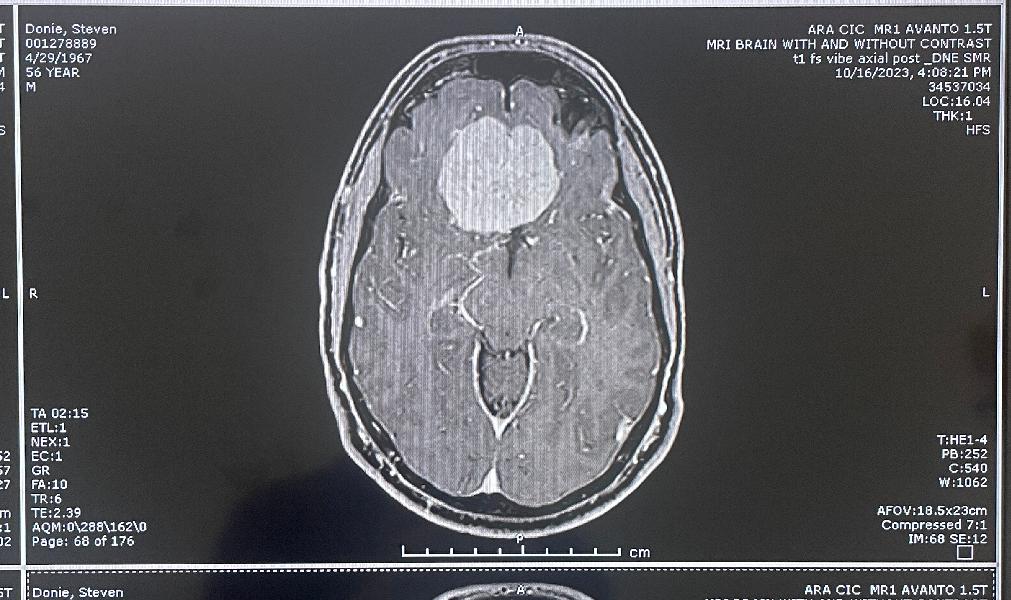

Another clear top view

more MRI